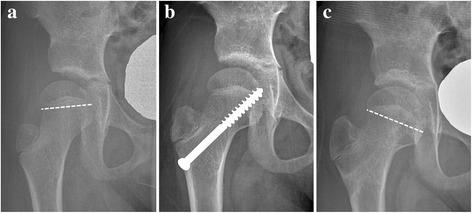

METHODS

Eighteen hips (18 patients) having caput valgum treated with screw hemi-epiphysiodesis were followed for more than 2 years, and were included in this study. The mean age at the time of the index operation was 8.3 years (range, 4.3 to 10.7 years) and age at the latest follow-up was 12.2 years (range, 9.4 to 16.4 years). The screw in 5 hips was changed into a longer one at postoperative 21.8 months (range, 14 to 29 months) because the proximal femur outgrew the screw. The screws in 11 hips were removed at the mean age of 10.9 years (range, 8.0 to 14.5 years). We retrospectively analyzed the change in various radiologic parameters over time.

The mean Hilgenreiner-epiphyseal angle (HEA) of the operated side was 5.1 ± 11.3° preoperatively, and increased to 20.6 ± 11.3° at the latest follow-up (p = 0.001). The mean difference of the HEA between the operated and contralateral sides was 16.9 ± 15.1° preoperatively, which decreased to 2.4 ± 12.4° at the latest follow-up (p = 0.008). The mean articulo-trochanteric distance of the operated side, which was 3.2 ± 5.5 mm longer than that of the contralateral side preoperatively, became 5.6 ± 9.1 mm shorter at the latest follow-up (p = 0.001). The ratio of femoral neck length of the operated side to that of the contralateral side decreased over the follow-up period. Acetabular shape as measured by the Sharp angle and acetabular roof angle and femoral head coverage as measured by lateral center-edge angle did not change significantly by the index operation. The ratio of medial joint space width of the operated side to that of the contralateral side did not change significantly.

CONCLUSIONS

Screw medial hemi-epiphysiodesis can effectively correct caput valgum associated with DDH. However, this technique remains coxa brevis and does not seem to significantly affect acetabular morphology or reduce subluxation.